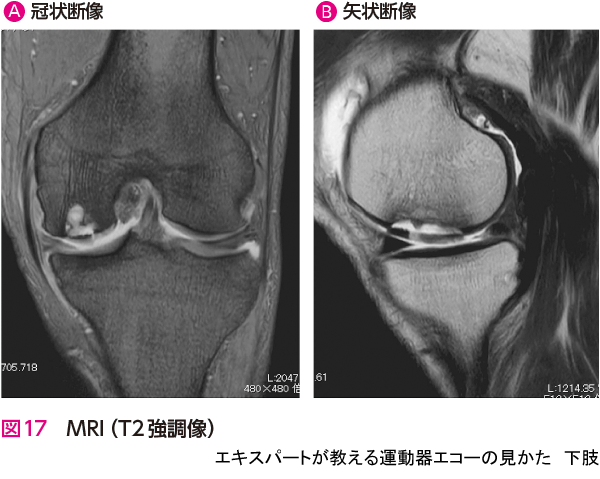

症例 7大腿骨内顆軟骨損傷